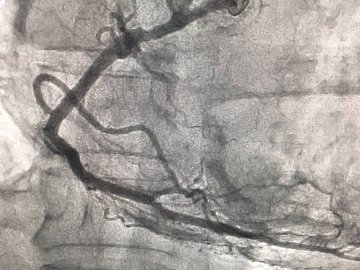

"Сьогодні нашими лікарями за допомогою сучасного ангіографа урнентно проведено стентування коронарних артерій хворому П. з приводу інфаркту міокарда.

Врятоване ще одне життя!!!",- йдеться в дописі.